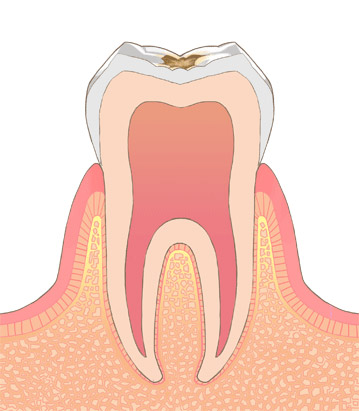

歯の表面のエナメル質が溶け始めた段階のむし歯です。痛みがなく、ついつい放っておきがちです。

むし歯箇所のみ削り、充填や詰め物で埋めます。